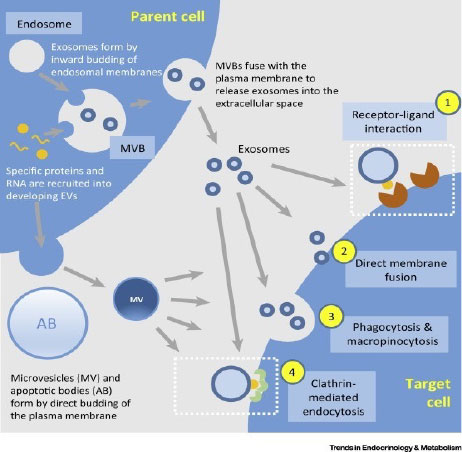

When exosomes are delivered directly into an affected joint, they start signaling to the cells to return to healthy function.

当外泌体直接输送到受影响的关节时,它们开始向细胞发出信号以恢复健康功能。

They send proteins into the walls of the cells telling the cells how to regulate themselves.

它们将蛋白质送入细胞壁,告诉细胞如何自我调节。

There are two stages to the body’s response. In the first stage, which happens almost immediately, the inflammatory response is turned off. In the second stage, the exosomes basically tell the cells how to regulate themselves correctly in the future, leading to long-term relief.

身体的反应有两个阶段。 在几乎立即发生的第一阶段,炎症反应被关闭。 在第二阶段,外泌体基本上告诉细胞未来如何正确调节自身,从而导致长期缓解。

As researchers have now concluded, it’s the exosomes stem cells release, rather than the cells themselves, that impart the regenerative benefit.

正如研究人员现在得出的结论,赋予再生益处的是外泌体干细胞释放,而不是细胞本身。